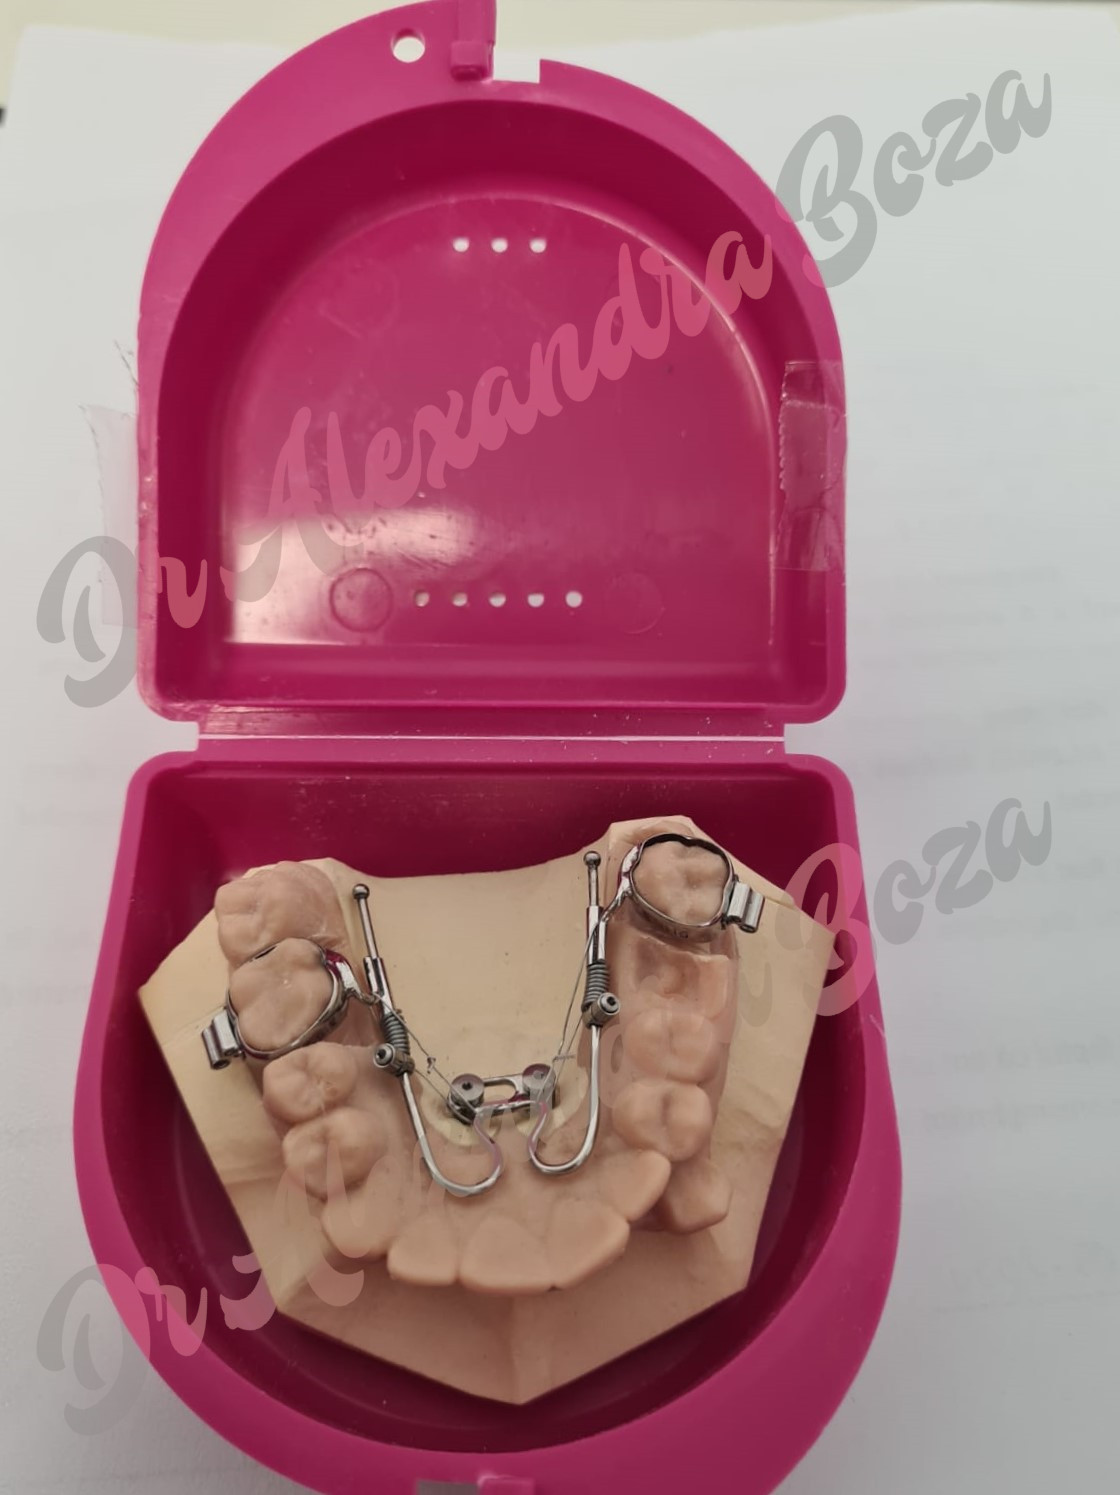

Aparate dentare mobile

Aparatele dentare mobile sunt indicate copiilor pana la varsta de 11-12 ani, inainte de eruptia tuturor dintilor definitivi.

Ele sunt eficiente in perioada de crestere a copilului cand pot influenta directia de crestere a maxilarelor, corectand astfel anomalii care presupun pozitionarea incorecta a acestora.

De asemenea, pot stimula dezvoltarea maxilarelor (cu ajutorul unor suruburi atasate pe aparat) favorizand astfel, crearea spatiului pentru alinierea dintilor pe arcada si dirijand eruptia lor in pozitia corecta.